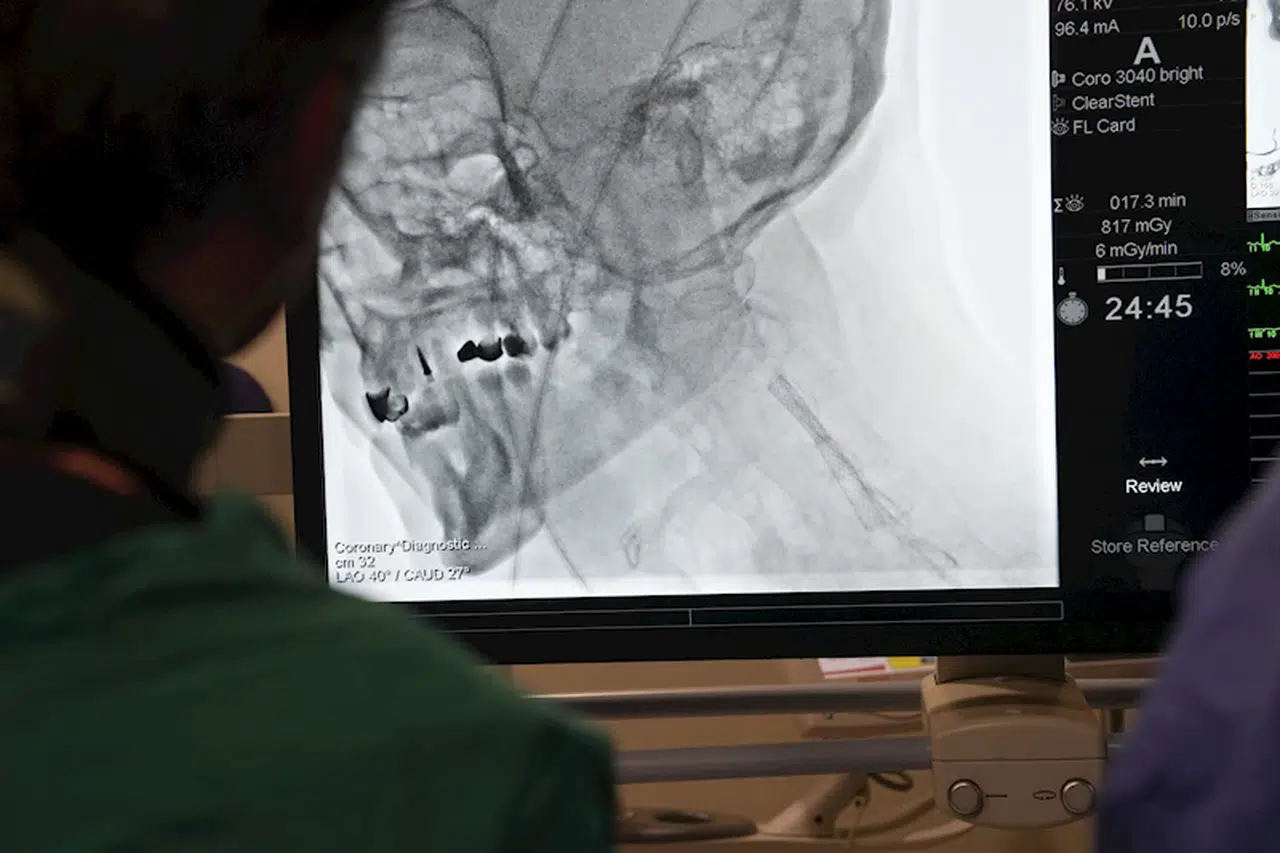

Tuğçe ODABAŞI-Fırat ALKIZ/İSTANBUL,(DHA)- Kardiyoloji uzmanları, yurt dışından gelen doktorlara yönelik ‘İleri Stent Teknikleri’ ve ‘Kronik Damar Açma’ alanlarında eğitim verdi. Prof. Dr. Ertuğrul Okuyan öncülüğünde gerçekleşen eğitim sırasında teorik bilgilerin yanı sıra, canlı operasyonlarla betonlaşmış damarlar açıldı.

Medipol Sağlık Grubu’nun düzenlediği ve bugün başlayan program, Kardiyoloji Uzmanı Prof. Dr. Ertuğrul Okuyan liderliğinde gerçekleştiriliyor. Özellikle Mısır, Pakistan, Tunus ve Cezayir gibi ülkelerden gelen doktorlara modern tıp alanındaki yenilikler ve ileri teknikler aktarıldı. ‘İleri Stent Teknikleri’ ve ‘Kronik Damar Açma’ gibi uygulamalar tüm detaylarıyla paylaşılırken, katılımcılara hem teorik bilgiler hem de canlı operasyon deneyimleri sunuldu. Eğitimler yarın da devam edecek.

Prof. Dr. Ertuğrul Okuyan, bugün başlayan ve 2 gün sürecek olan eğitim programının içeriği ve uyguladıkları ‘İleri Stent Teknikleri’ konusunda da önemli bilgiler paylaştı. Prof. Dr. Okuyan, Türkiye’nin kardiyovasküler girişimlerde dünya standartlarını yakaladığını ve birçok şehirde hem kamu hem özel sektörde bu alanda ileri düzey merkezlere sahip olduğunu belirterek, “Ülkemiz, kardiyoloji ve kardiyovasküler alanında çok iyi bir düzeye ulaştı. Artık Amerika Birleşik Devletleri veya Avrupa’nın önde gelen ülkelerinde yapılan her türlü işlem, Türkiye’de de büyük başarıyla uygulanabiliyor. Hekimlerimiz çok yetenekli, deneyimli ve sahip olduğumuz teknolojik altyapı dünya standartlarında” dedi.

‘BETONLAŞMIŞ VE SERTLEŞMİŞ DAMARLARI AÇMAK MÜMKÜN’

Prof. Dr. Okuyan, geleneksel yöntemlerle açılması mümkün olmayan damar tıkanıklıklarının, ileri teknikler sayesinde başarıyla tedavi edilebildiğini de söyleyerek, “Eskiden, çatallanma veya dallanma noktalarındaki darlıklar ya da uzun süredir tıkalı, betonlaşmış, kireçlenmiş damarlar açılamıyordu. Ancak günümüzde kullandığımız ileri teknikler sayesinde bu sorunların üstesinden geliyoruz” diye konuştu.

“Bu tekniklerin temelinde, damar içi ultrason gibi görüntüleme yöntemleriyle damar morfolojisinin detaylı bir şekilde incelenmesi ve özel cihazların yardımıyla tıkanıklıkların açılması yer alıyor” diyen Prof. Dr. Okuyan, “Damar içi tıraşlama yöntemleri, taşırma kateterleri ve özel malzemelerle artık eskiden açamadığımız damarları açabiliyoruz. Bu işlemler, ileri stentleme teknikleri olarak adlandırılıyor” ifadelerini kullandı.